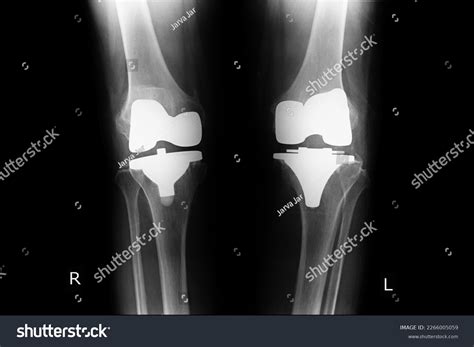

• Implant Placement: Securing the metal and plastic components that act as the new joint.

Many patients worry about pain management, the appearance of the surgical site, and the longevity of the implant. By watching a professional Total Knee Replacement video, you can witness the precision involved in modern robotics-assisted surgery, which often leads to smaller incisions and more accurate alignment. This knowledge helps address common misconceptions, such as the idea that the entire knee is “replaced.” In reality, the procedure is more of a resurfacing of the joint, where only the diseased bone and cartilage are removed and replaced with high-durability prosthetic materials.

Modern advancements have revolutionized the orthopedic field. If you search for a recent Total Knee Replacement video, you will likely encounter techniques involving computer navigation or robotic arms. These tools allow surgeons to customize the fit of the implant to your specific anatomy, potentially increasing the lifespan of the prosthetic and improving overall joint function. Watching these advanced techniques can provide extra peace of mind, demonstrating that modern surgery is highly personalized rather than a “one size fits all” operation.